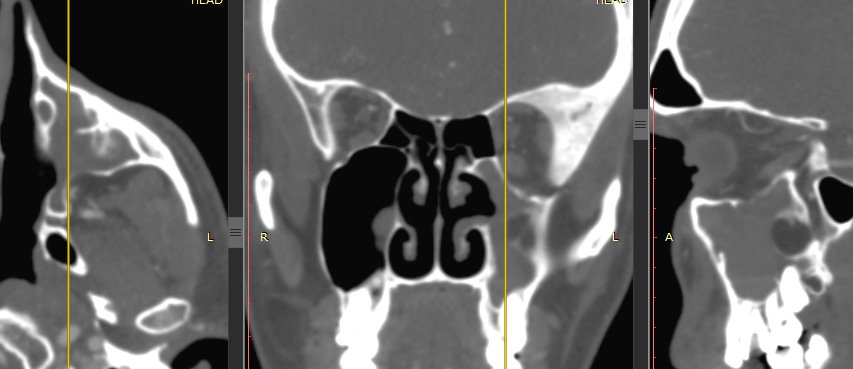

Пациентка Э., МСКТ выполнялась в предоперационном периоде. По результатам исследования получено следующее заключение: КТ-картина новообразования верхнечелюстной пазухи слева на фоне гиперостоза ее стенок, деформация нижней стенки глазницы, утолщение слизистой ячеек решетчатой кости (рис. 1). Интерпретация рентгенологами данных предвещала агрессивное хирургическое вмешательство с широким операционным доступом к нижней стенке орбиты и созданию костного окна более чем в 1 см диаметром.

Рис. 1. Пациентка Э., предоперационное МСКТ, вид ВЧП слева

По данным КЛКТ получен следующий интерфейс: диффузное снижение пневматизации ВЧП слева, инородное тело (вероятнее всего, пломбировочный материал) в дистальной трети дна ВЧП слева, кистогранулемы в проекции верхушек корней зубов 2.5 и 2.7, целостность нижней стенки орбиты не нарушена, костно-дистрофической картины не визуализировано (рис. 2).

Рис. 2. Пациентка Э., предоперационное КЛКТ, вид ВЧП слева